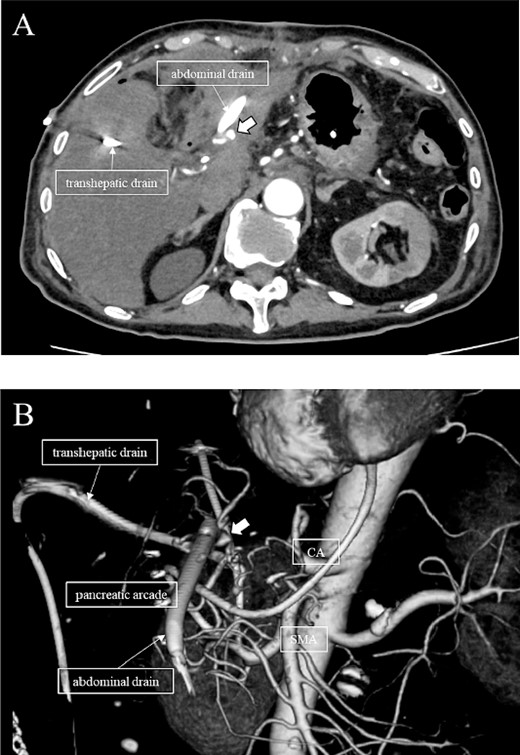

A 76-year-old man underwent DP-CAR after eight courses of gemcitabine and nab-paclitaxel therapy as preoperative chemotherapy for pancreatic body cancer with celiac artery invasion (Fig. 1). As the celiac axis had not invaded into the bifurcation of the left gastric artery, a modified DP-CAR (left gastric-preserving) was performed. Although post operative pancreatic fistula (POPF) developed on postoperative Day (POD) 5, and biliary fistula developed on POD 17. Bile leak was thought to be caused by the rupture of the choledochal duct due to bile duct ischemia caused by CHA transection. Subsequently, both the POPF and biliary fistulae were drained and fistulated. However, on POD 47, the drainage fluid became bloody. Contrast-enhanced computed tomography (CeCT) revealed a pseudoaneurysm at the junction of the gastroduodenal artery (GDA) and proper hepatic artery (PHA) (Fig. 2A and B).

(A, B) CT on postoperative day 48. Contrast-enhanced CT showing a pseudoaneurysm at junction of the GDA and PHA (arrow).